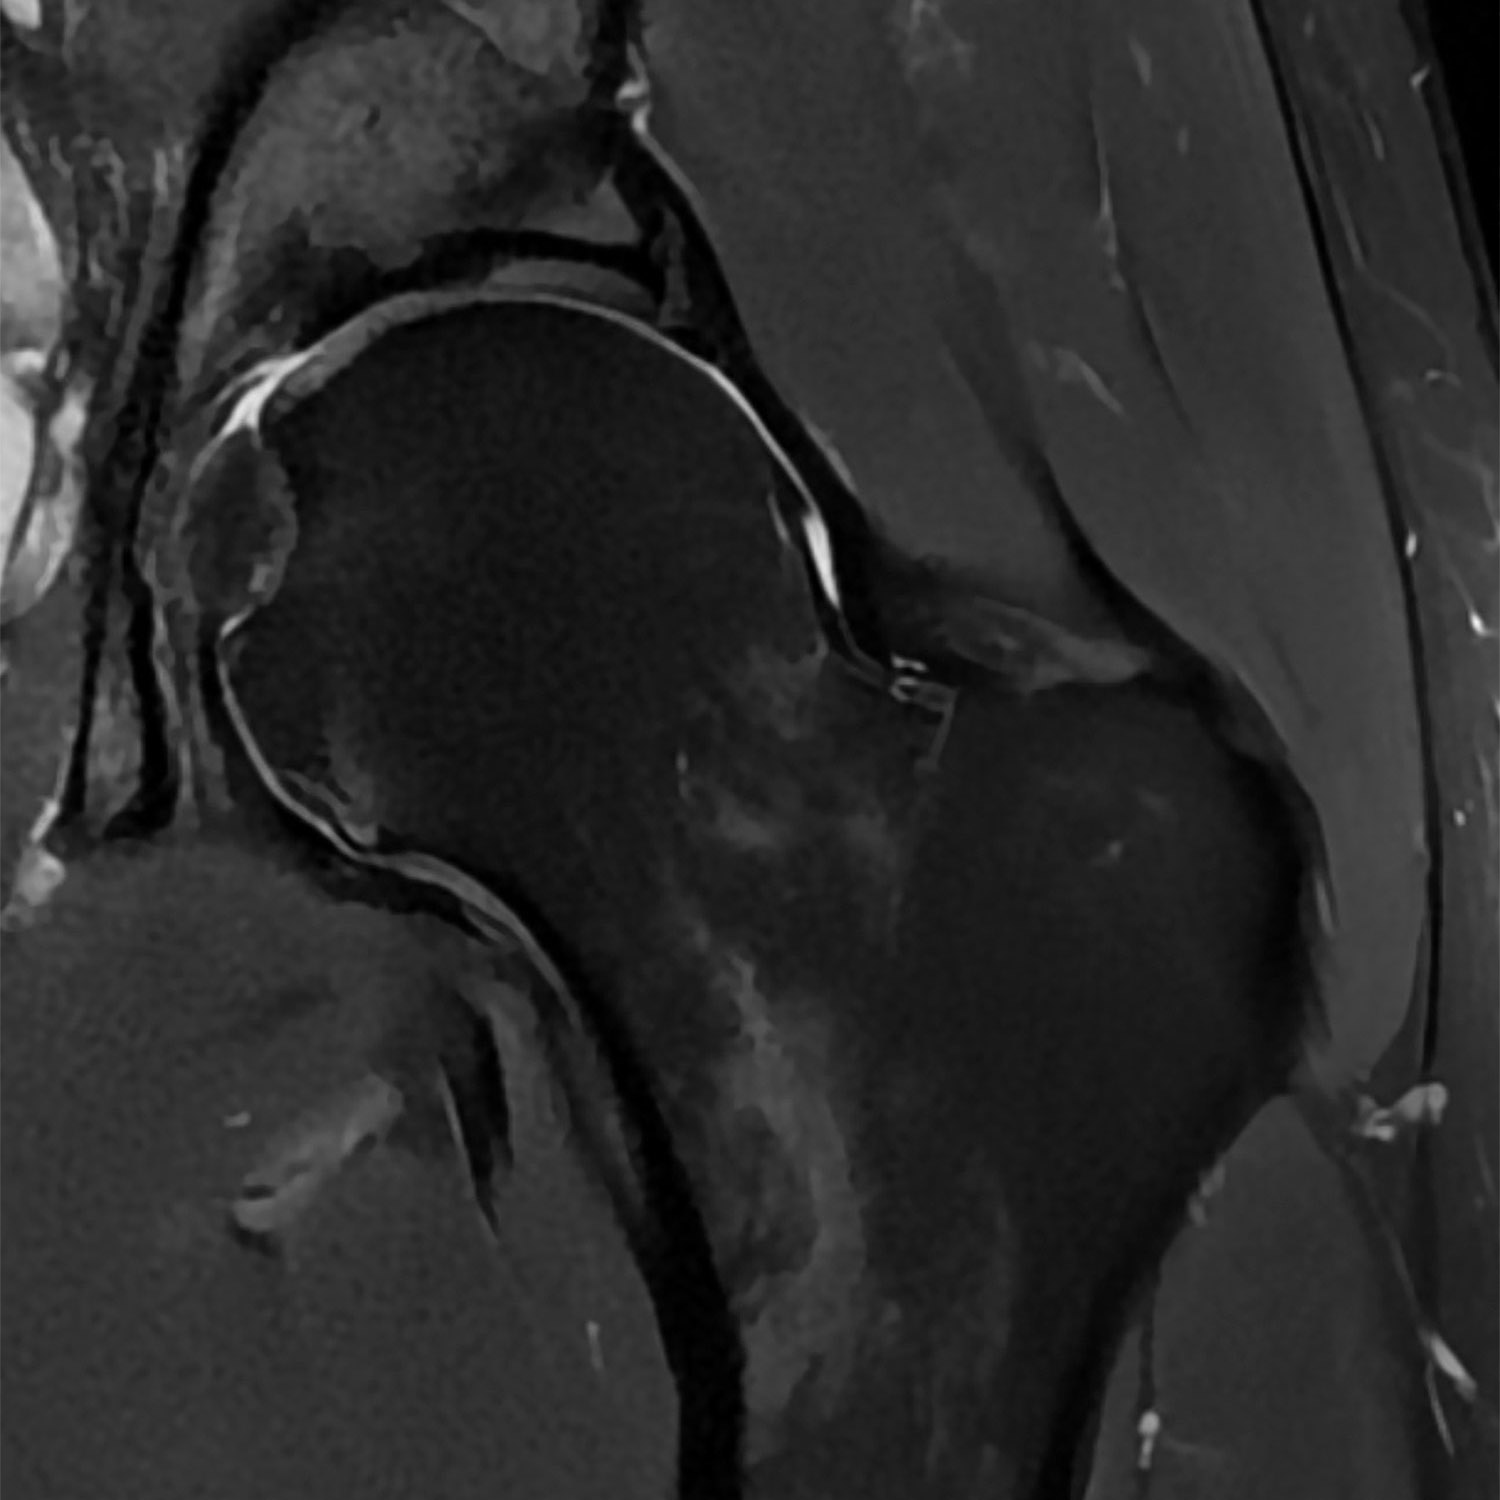

- du genou, le l'épaule, de la hanche et du bassin, du pied, de la cheville, des doigts, des articulations et des os.